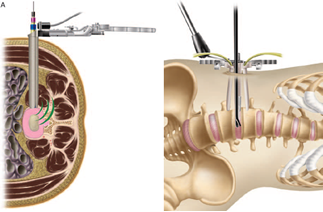

頚椎疾患に対する椎弓形成術・除圧固定術

頚椎椎弓形成術(第3頚椎ー第7頚椎)後方からの模式図

A:自家骨を用いる場合

B:人工骨を用いる場合

頚椎症性脊髄症の中で脊椎内視鏡下手術の適応でないもの、後縦靭帯骨化症による脊髄症に対して頚椎後方から椎弓形成術(脊柱管拡大術)を実施しています。変形が高度のもの椎間が力学的に不安定なものに対しては最新の手術器械を使用しての固定術を併用しております。術後療法や入院期間は病態や術式により異なりますが、概ね2-4週間です。